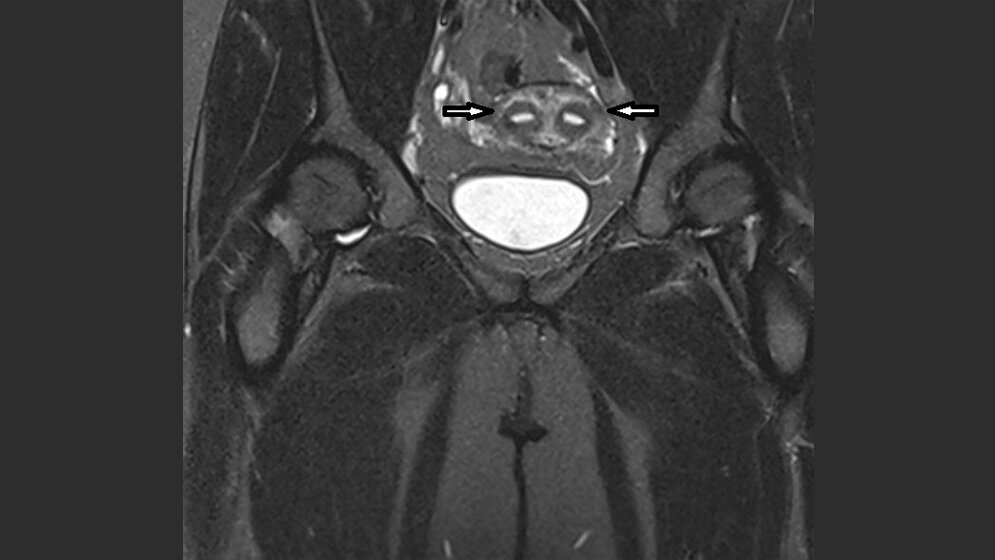

Das Vorkommen uteriner Malformationen in der Bevölkerung liegt bei 2–4 %. Sie können zu Fertilitätsproblemen und Komplikationen während der Schwangerschaft führen. Es gibt zahlreiche urogenitale Anomalien, die mit einem Uterus bicornis assoziiert sind.

The prevalence of uterine malformations in the general population is 2–4 %. The incidence of uterine malformations leads to impaired fertility and obstetric complications. There are many congenital urogenital anomalies that are associated with the uterus bicornis.